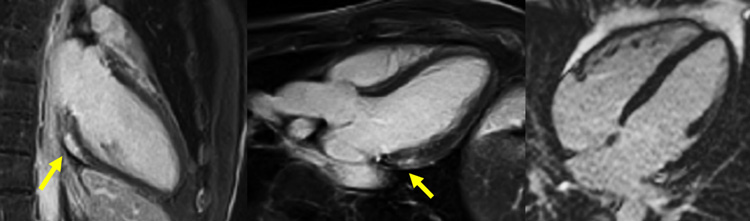

Figure 6A : Séquence T2 STIR - Coupes petit-axe

Figure 6B : Séquence T2 STIR - Coupes long-axe

Présence d’une zone d’œdème myocardique inféro-latéro-basale et inféro-basale avec un hyper-signal T2 (zones blanches, flèches jaunes), comparé au reste du myocarde en iso-signal (le reste du myocarde est gris).

Astuce quant à l'analyse du T2-STIR

- La séquence de T2-STIR inclut une préparation de l’aimantation qui permet d’annuler le gras et le sang. Ainsi, on peut retenir que la seule entité qui est théoriquement censée être en hypersignal est l’œdème myocardique.

- Cependant, veuillez noter ici qu’une partie du sang n’a pas correctement été annulée au niveau des apex du VG et du VD. Il s’agit d’un artéfact classique sur ce type de séquence, qui correspond à des globules rouges moins en mouvement au niveau de l’apex, et qui sont donc moins bien annulés.

- Enfin, retenez que le principal avantage de la séquence de T2-STIR par rapport au T2 mapping est de pouvoir visualiser un éventuel œdème au niveau du péricarde ! Cependant, ici, malgré la douleur d’allure péricarditique cliniquement, on ne note pas d’hypersignal du péricarde. En effet, la sensibilité de l’IRM cardiaque n’est pas de 100 % pour le diagnostic de péricardite aiguë !

Figure 4A : Séquence de rehaussement tardif - Coupes petit-axe

Figure 4B : Séquence de rehaussement tardif - Coupes long-axes

Présence d’une zone de rehaussement tardif sous-épicardique aux niveaux inféro-latéro-basal et inféro-basal (zones blanches, flèches jaunes) comparée au reste du myocarde (noir).

Retenez le dogme selon lequel le muscle cardiaque sain apparaît toujours « noir » sur les séquences de rehaussement tardif.

Visualisation d’un rehaussement myocardique systolique à prédominance sous-épicardique sur les cinés long-axe (2 cavités et 3 cavités) acquises après injection de gadolinium. C’est un signe assez évocateur d’œdème myocardique, qui est souvent retrouvé en cas de myocardite aiguë.